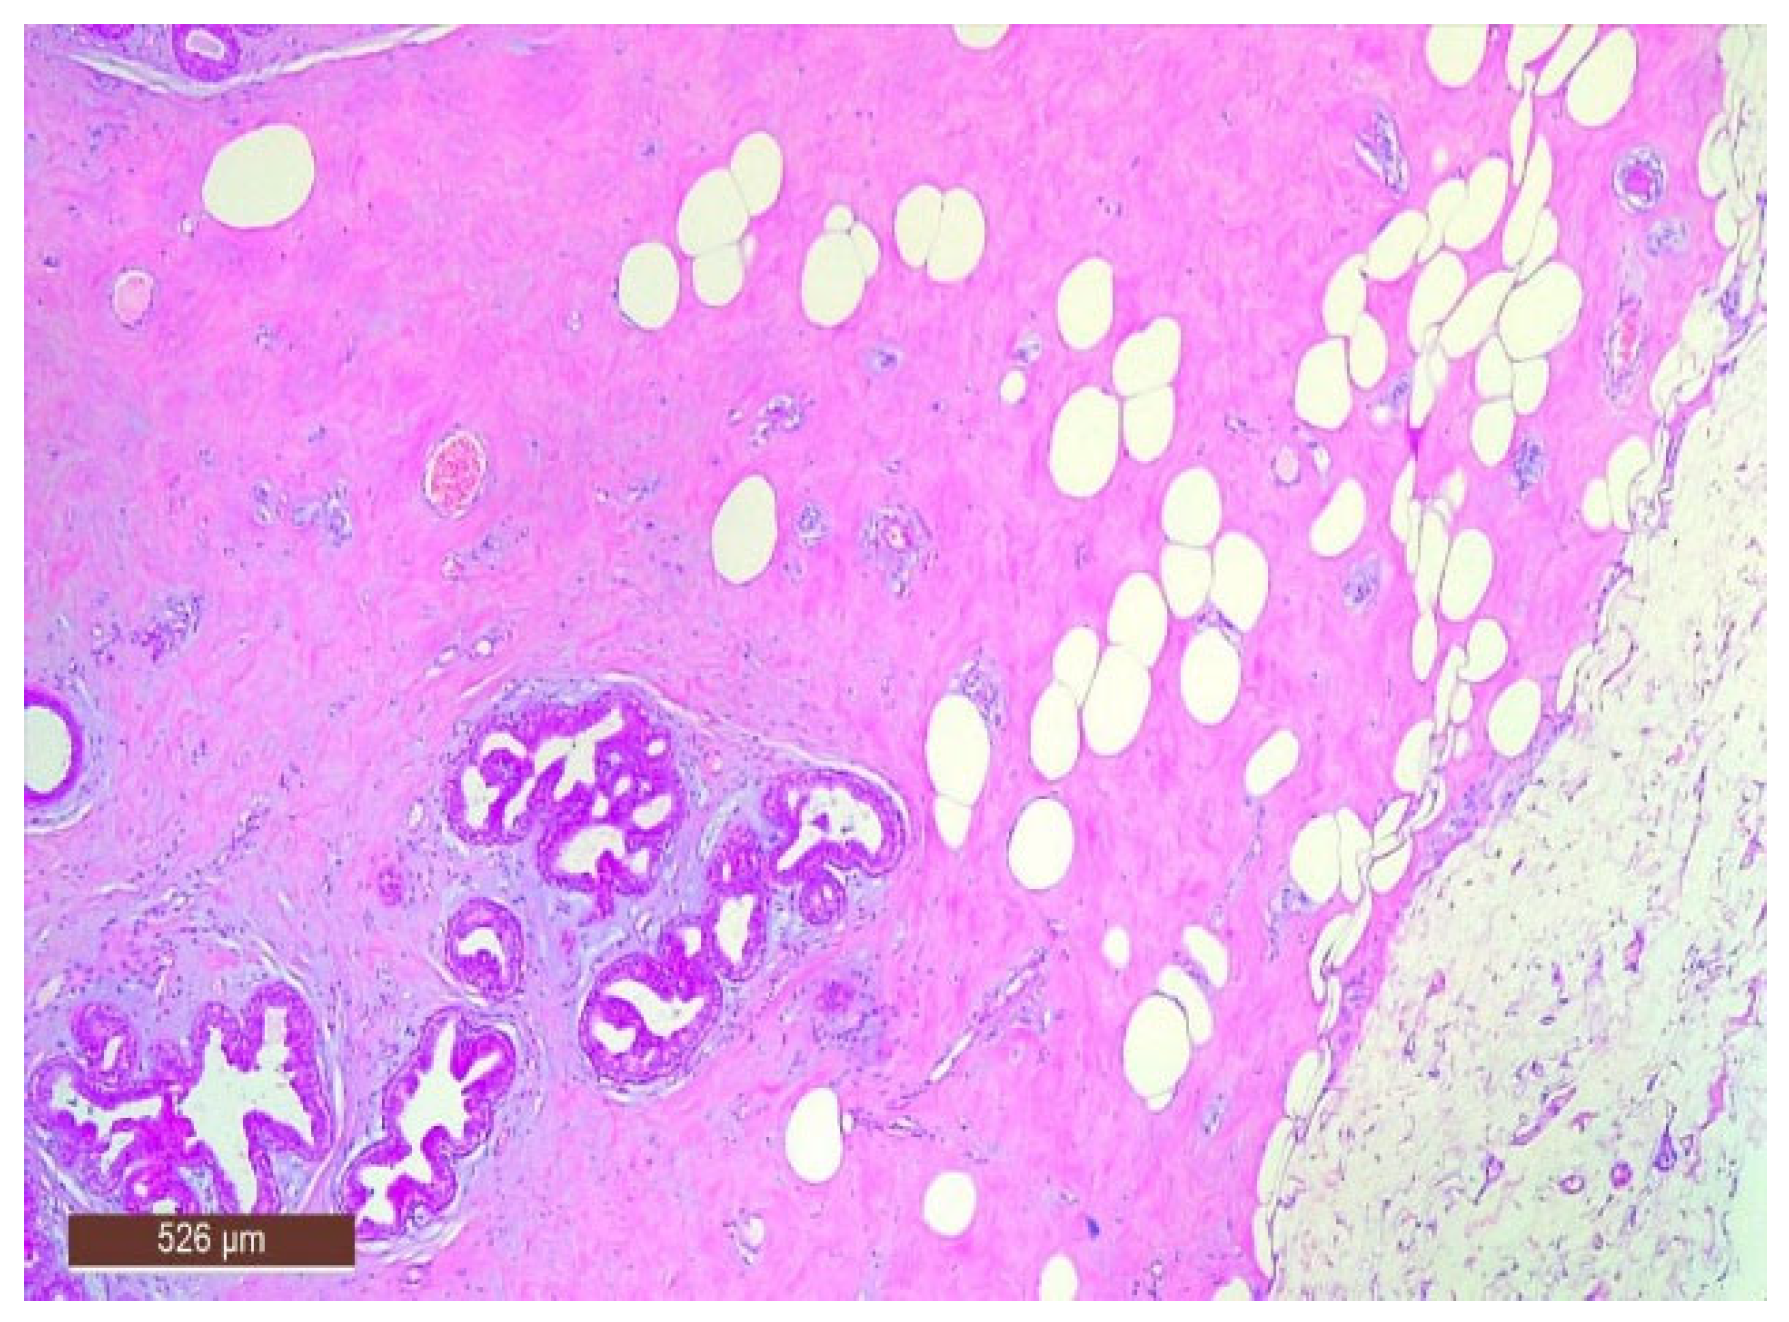

On microscopic examination, a hamartoma may exhibit three predominant components: glandular, fibrous and adipose (Figure 7). Epithelial components such as ducts and lobules are generally normal, featuring a single layer of epithelium overlying the myoepithelial cells. The fibrous component was composed of connective tissue stroma with a delicate connective tissue capsule (Figure 8). Additionally, the ducts within the hamartoma may display apocrine metaplasia (Figure 9).

Adipose tissue in the hamartoma may be prominently proliferative (Figure 11), which can complicate the differential diagnosis with a lipoma on ultrasound. Conversely, the adipose component can also be nearly absent.

Figure 7. Hamartoma—histological structure (HE ×40).

Figure 11. Hamartoma with fat cells interspersed within the lesion (HE ×40).